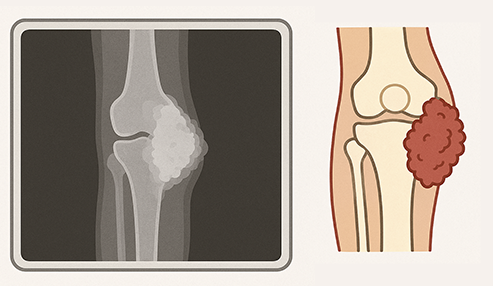

骨肉腫は膝、肩などの骨に発生する、10代のこどもに多い悪性腫瘍です。日本では年間200人程度が新たに診断されます。まれな病気ですが命に関わる病気なので、小児の膝痛を診るときに整形外科医は常に念頭においています。成長痛だろうと放置したり、マッサージをしたりすると病状は悪化してしまいます。*4

膝に発生した骨肉腫(イメージ)